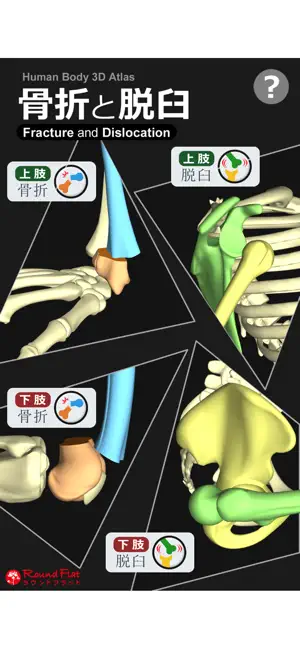

上肢、下肢の骨折と脱臼を3DCGのモデルとアニメーションで再現した骨折と脱臼を学ぶアプリ。

回転、移動、拡大縮小が思いのまま。3DCGアニメーションも付いています。

書籍や図譜では分かりにくかった骨折・脱臼の発生機転や転位が立体的に理解できます。

・上肢・下肢の骨折・脱臼を360°好きなアングルで!

・骨折・脱臼の発生機転をCGアニメーションで再現

・発生機転のワンポイント解説付